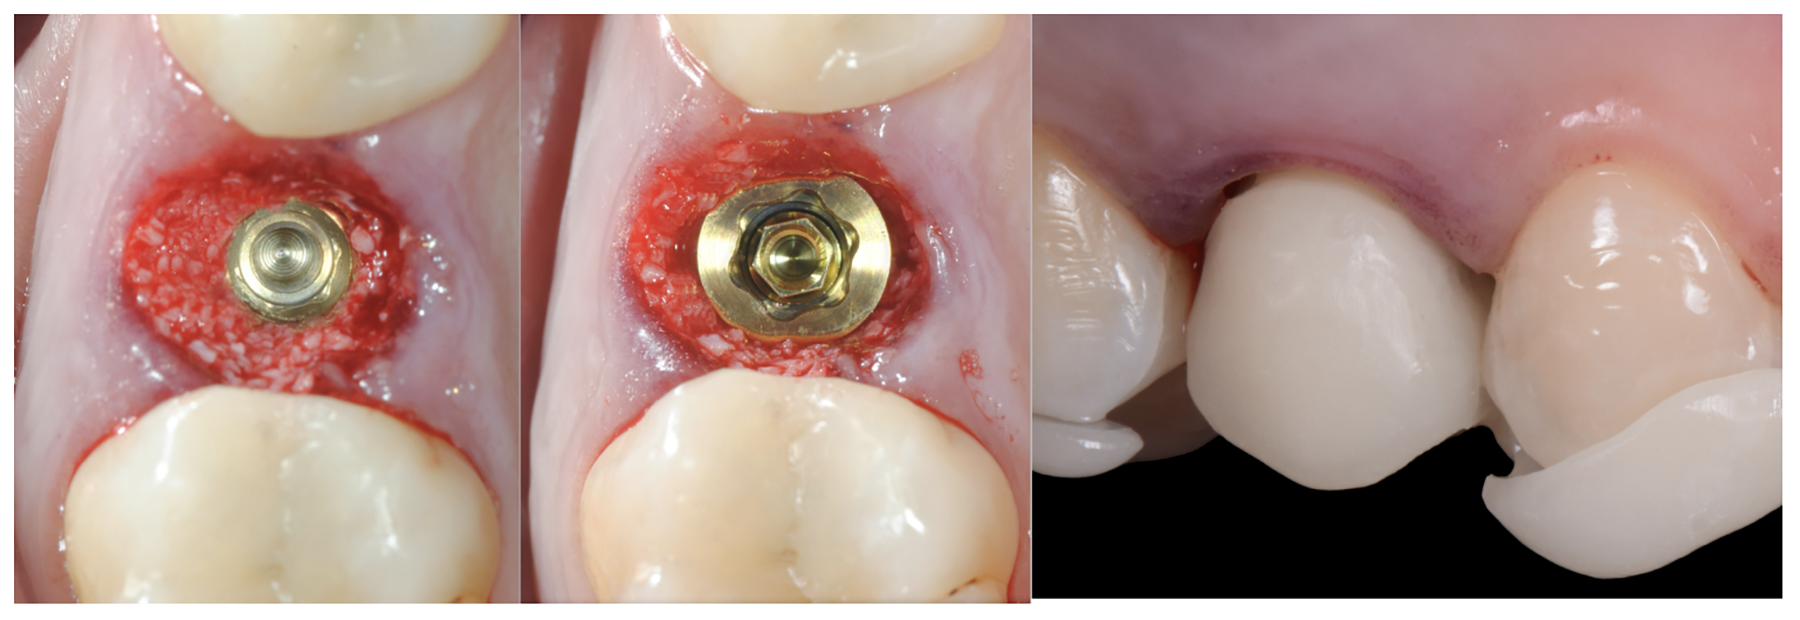

Finally, once the proper 3D position of the implants has been identified, the abutment placement protocol to be used should be evaluated. The "one abutment/one time" approach4,6,8,17 allows soft tissues to adhere firmly onto the surface of titanium abutments, thereby improving soft tissue response and bone stability (Figure 4 and Figure 7 through Figure 14 ). This approach avoids multiple connections and disconnections at the bone interface and favors undisturbed bone and soft tissue healing.4-7